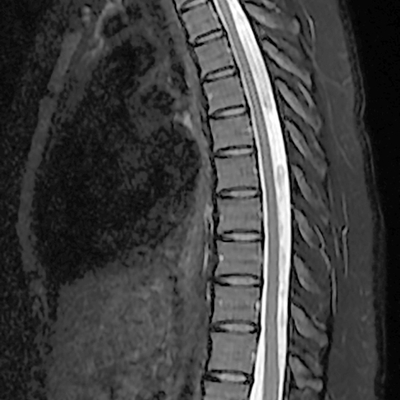

Click on an image below to view more info.